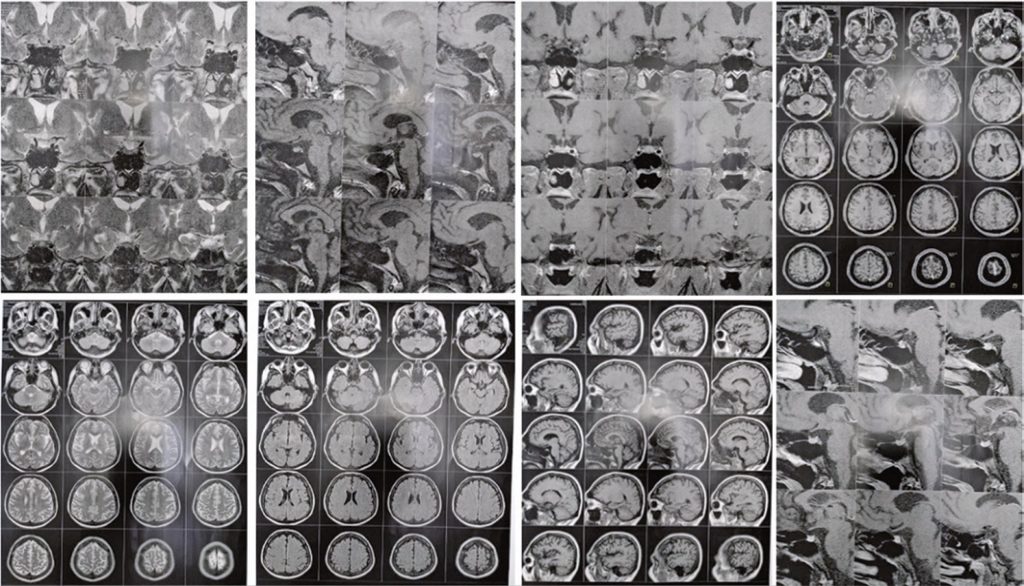

Idiopathic partial central diabetes insipidus

Diabetes insipidus is a rare disorder characterized by the inability to concentrate urine, which results in hypotonic urine and increased urinary volume. It may occur because of antidiuretic hormone deficiency or resistance to its action in the renal tubules. When there is a deficiency in the synthesis of antidiuretic hormones, diabetes insipidus is called central; when there is resistance to its action in the renal tubules, it is said to be nephrogenic. We report a case of idiopathic partial central diabetes insipidus and highlight the management and treatment of the disease.